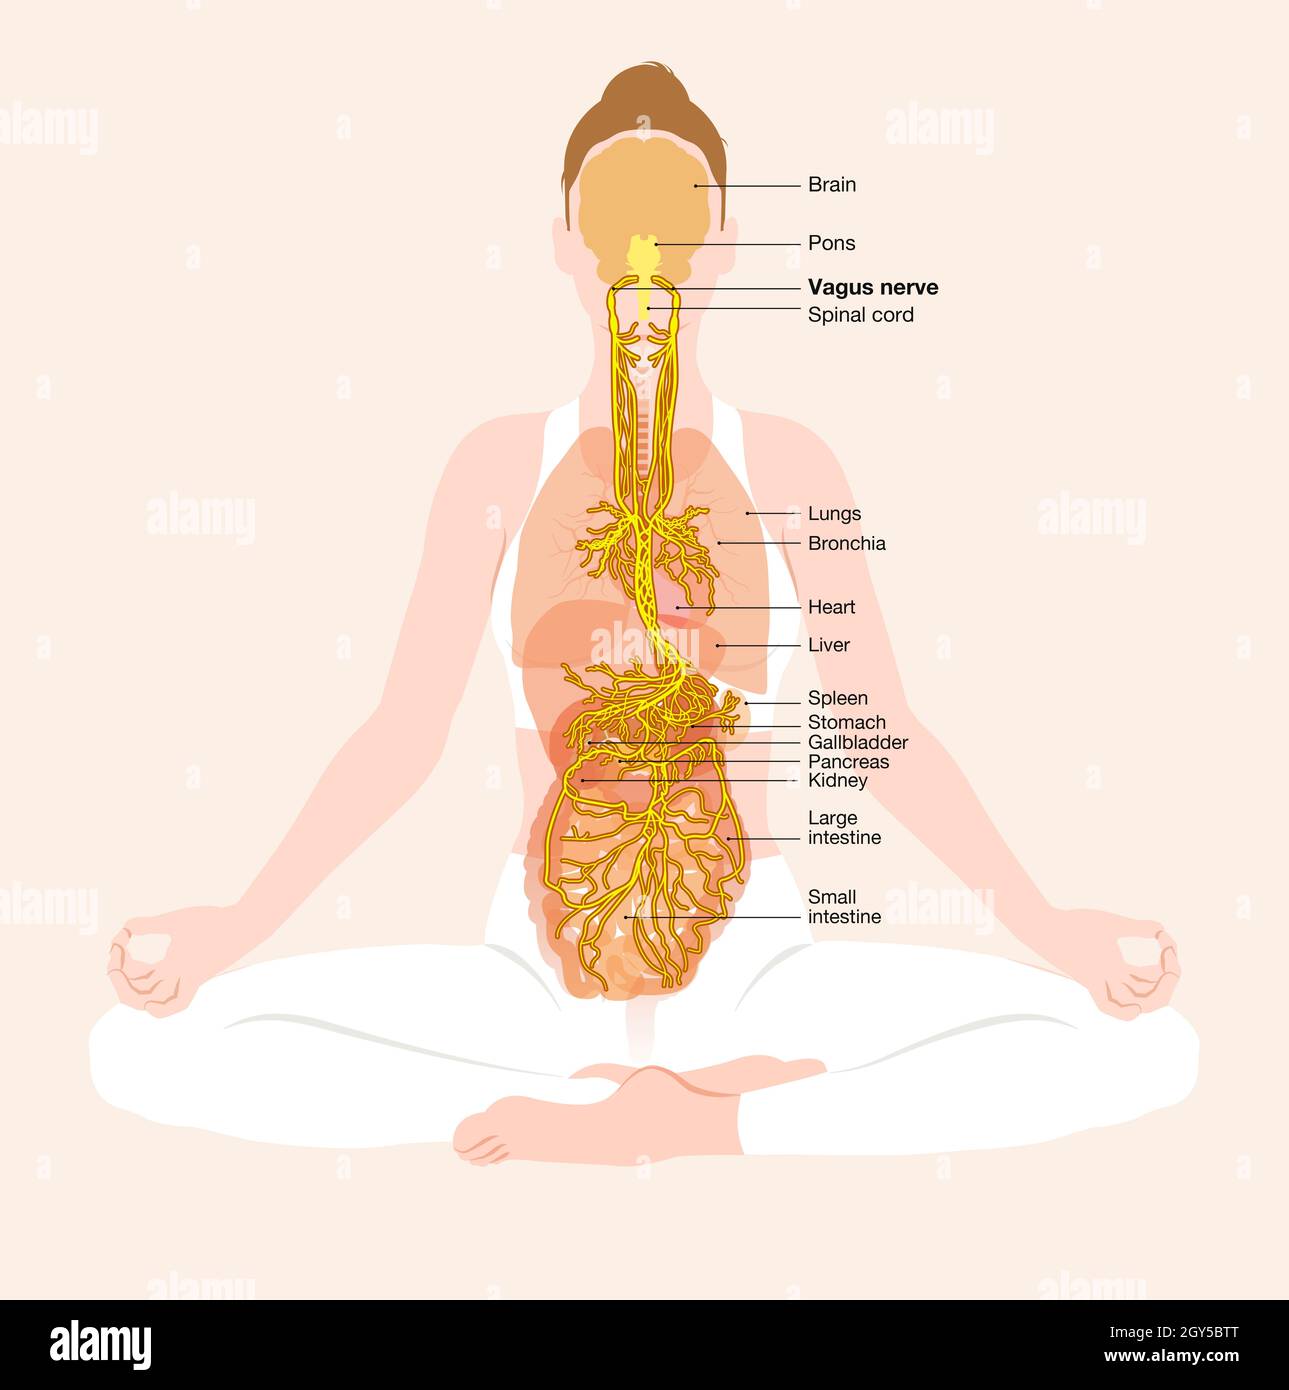

This illustration showing brain and active vagus nerve (tenth cranial nerve) with lungs, heart, stomach and digestive tract Stock Photohttps://www.alamy.com/image-license-details/?v=1https://www.alamy.com/this-illustration-showing-brain-and-active-vagus-nerve-tenth-cranial-nerve-with-lungs-heart-stomach-and-digestive-tract-image446973989.html

This illustration showing brain and active vagus nerve (tenth cranial nerve) with lungs, heart, stomach and digestive tract Stock Photohttps://www.alamy.com/image-license-details/?v=1https://www.alamy.com/this-illustration-showing-brain-and-active-vagus-nerve-tenth-cranial-nerve-with-lungs-heart-stomach-and-digestive-tract-image446973989.htmlRF2GY5BTN–This illustration showing brain and active vagus nerve (tenth cranial nerve) with lungs, heart, stomach and digestive tract

This illustration showing brain and active vagus nerve (tenth cranial nerve) with lungs, heart, stomach and digestive tract Stock Photohttps://www.alamy.com/image-license-details/?v=1https://www.alamy.com/this-illustration-showing-brain-and-active-vagus-nerve-tenth-cranial-nerve-with-lungs-heart-stomach-and-digestive-tract-image446973988.html

This illustration showing brain and active vagus nerve (tenth cranial nerve) with lungs, heart, stomach and digestive tract Stock Photohttps://www.alamy.com/image-license-details/?v=1https://www.alamy.com/this-illustration-showing-brain-and-active-vagus-nerve-tenth-cranial-nerve-with-lungs-heart-stomach-and-digestive-tract-image446973988.htmlRF2GY5BTM–This illustration showing brain and active vagus nerve (tenth cranial nerve) with lungs, heart, stomach and digestive tract

This illustration showing brain and active vagus nerve (tenth cranial nerve) with lungs, heart, stomach and digestive tract Stock Photohttps://www.alamy.com/image-license-details/?v=1https://www.alamy.com/this-illustration-showing-brain-and-active-vagus-nerve-tenth-cranial-nerve-with-lungs-heart-stomach-and-digestive-tract-image446973992.html

This illustration showing brain and active vagus nerve (tenth cranial nerve) with lungs, heart, stomach and digestive tract Stock Photohttps://www.alamy.com/image-license-details/?v=1https://www.alamy.com/this-illustration-showing-brain-and-active-vagus-nerve-tenth-cranial-nerve-with-lungs-heart-stomach-and-digestive-tract-image446973992.htmlRF2GY5BTT–This illustration showing brain and active vagus nerve (tenth cranial nerve) with lungs, heart, stomach and digestive tract